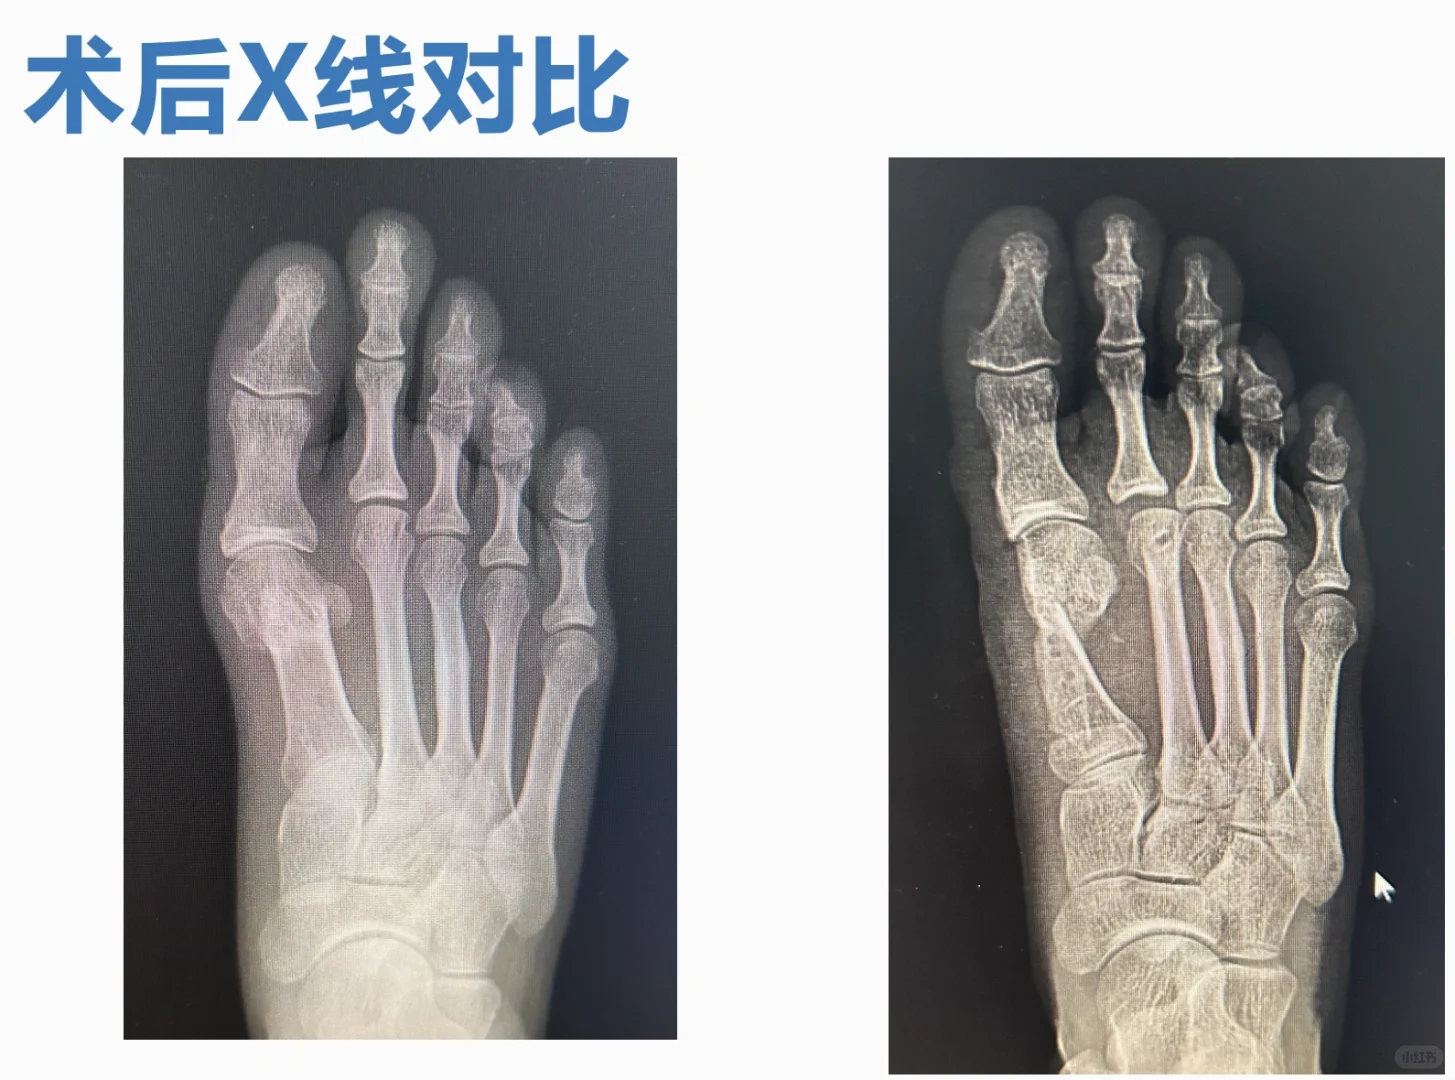

翻修的越来越多,难度也越来越大,但是,经验也越来越多。 微创术后的三种特殊畸形,已经彻底搞定了一种,还有一种在研究,另一种因为关节的毁损,目前看只能等人工关节了。 然而,大量的假患者仍然遍布这个平台。 翻修不光是外观问题,关节软骨、血运、长短、高低、旋转,一般讲,绝大部分无法恢复正常结构,只能针对症状处理了。